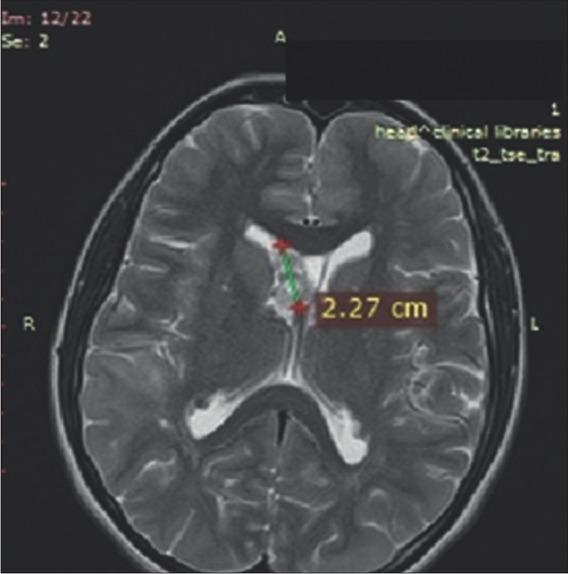

Figure 4